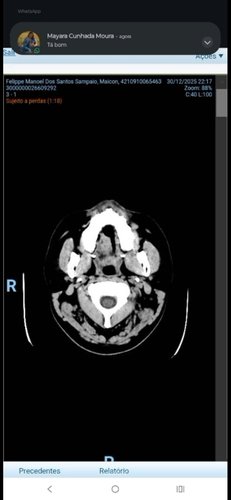

Como ele descobriu .há dois meses ele sentia forte dores de cabeça foi ao médico mas nenhum medicamento ajudava contra as dores Foi então que o médico pediu um exame específico uma tomografia é ali foi diagnosticado uma massa (Um tumor ) no cérebro no mesmo momento ele já foi internado no hospital local conseguiu uma vaga em um outro hospital no conjunto hospitalar Mandaqui zona norte de São Paulo e até o momento ele encontra internado esperando uma possível cirurgia peço ajuda de todos com qualquer valor para ajudar ele e a família Maicon é um homem trabalhador mas não trabalha de carteira assinada Ele trabalha por dia e recebe por dia por esse motivo Ele está internado e não conseguir trabalhar precisa mais ainda de nossa ajuda peço encarecidamente que nos ajude nesse momento difícil Deus abençoe